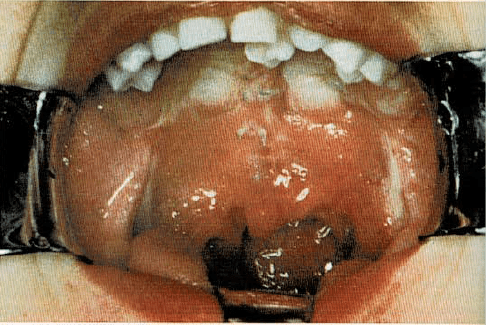

Fisura palatina

Es una abertura en el techo de la boca, que generalmente mantiene las cavidades bucal y nasal separadas. La abertura puede ser muy pequeña o por el contrario, tan grande que convierta ambas cavidades en una sola. Casi siempre la fisura se extiende al labio superior, además del paladar. En algunas ocasiones es hereditaria, pero lo más común es que algún proceso, antes del nacimiento del niño, interfiriera el desarrollo y soldadura normal de los mamelones que formarán la boca.

La fisura palatina es una hendidura del paladar (techo de la boca), de tipo congénito.

Se puedo arreglar por medio de una operación que une las dos partes de la fisura palatina.

El recién nacido con una fisura palatina puede tener dificultades para mamar y normalmente requerirá ser alimentado de forma particular. Además es de destacar que los niños con fisura palatina tienen tendencia a padecer infecciones del oído medio, por lo que precisan lavados cuidadosos efectuados a poca presión, a fin de evitar esta complicación.

El médico recomendará una operación correctora, que generalmente no se lleva a cabo hasta los dos años, o bien una prótesis dentaria, en lugar de la cirugía. El propósito es de dar buena apariencia a la cara del niño, capacitarle para mamar y hablar con normalidad y permitirle que tenga un desarrollo y crecimiento físico, emocional y social, normal.